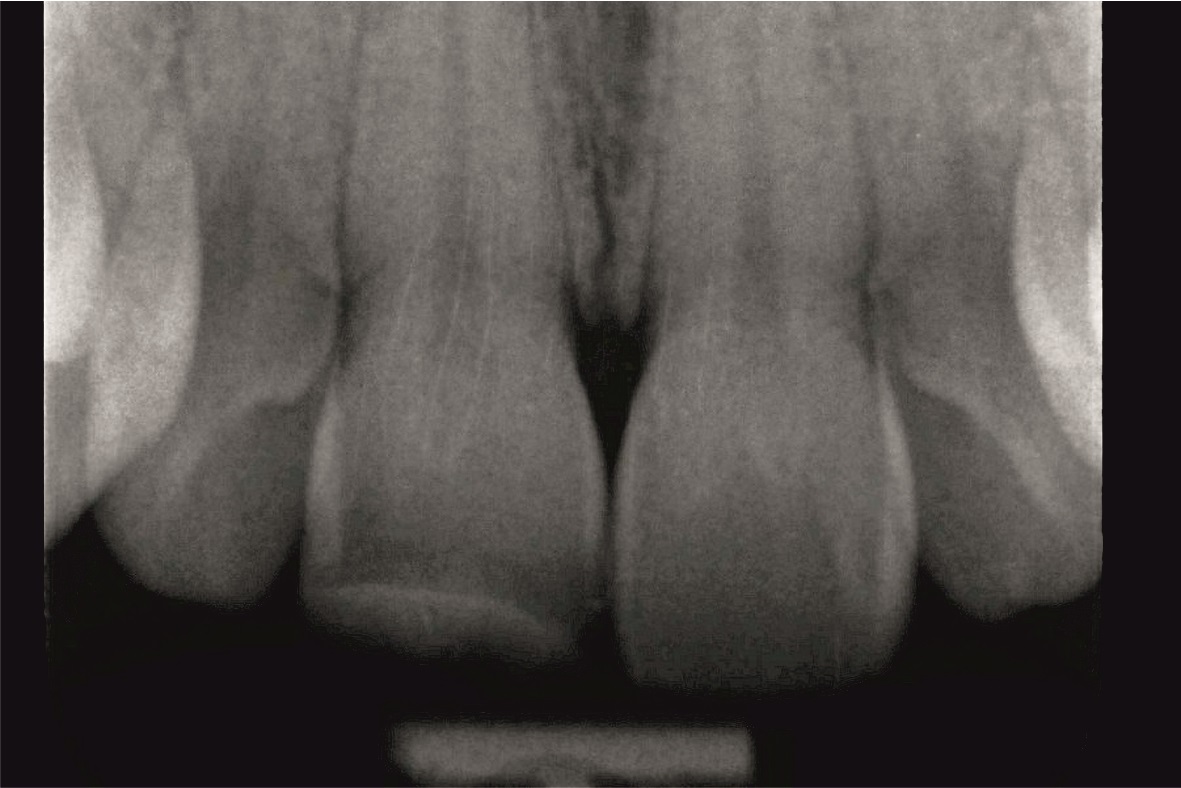

30-letni pacjent bez istotnego wywiadu medycznego zgłosił się w celu wymiany rekonstrukcji kompozytowej wykonanej przed 10 laty po doznanym wówczas urazie zęba 11. Ząb ten w badaniu klinicznym reagował na test żywotności i nie wykazywał zmian okołowierzchołkowych na zdjęciu rentgenowskim wykonanym w dniu badania (ryc. 1).